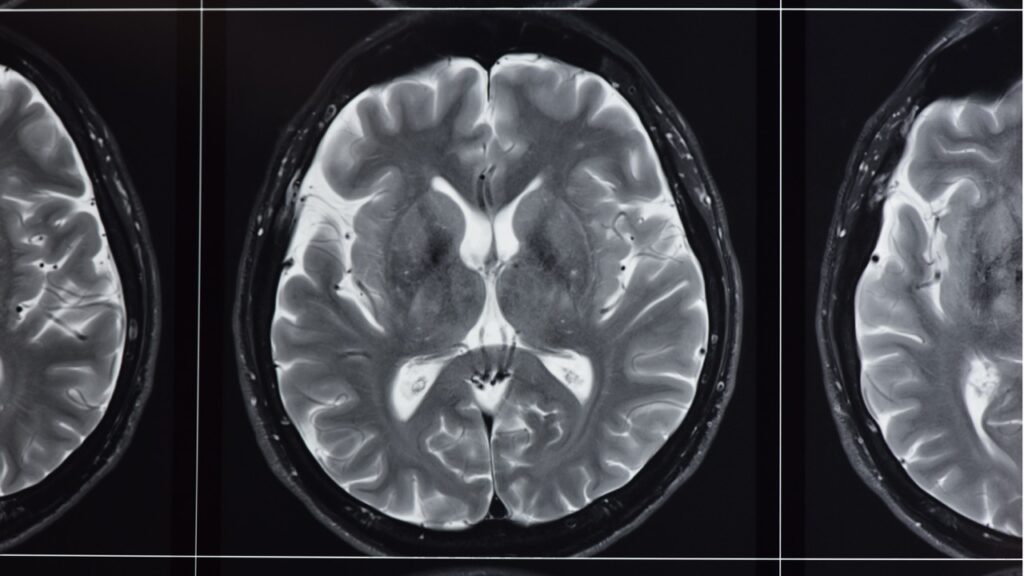

How a Spine MRI Can Help Diagnose Your Back Pain

Spine MRI for Back Pain: A Guide to Accurate Diagnosis Back pain can turn simple tasks into daily struggles. You wake up stiff, struggle to tie your shoes, and avoid activities you once enjoyed. When pain persists for weeks or months, you need answers about what’s causing your discomfort. A spine MRI for back pain […]